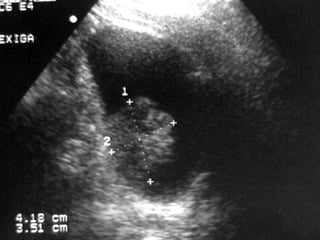

Câncer de Bexiga Estudos de imagens Diagnóstico Ultrassonografia Urografia excretora Estadiamento CT RNM Rx tórax  Cistoscopia + biópsia + biópsias randomizadas

Câncer de BexigaEstudos de imagens Diagnóstico Ultrassonografia Urografia excretora Estadiamento CT RNM Rx tórax Cistoscopia + biópsia + biópsias randomizadas